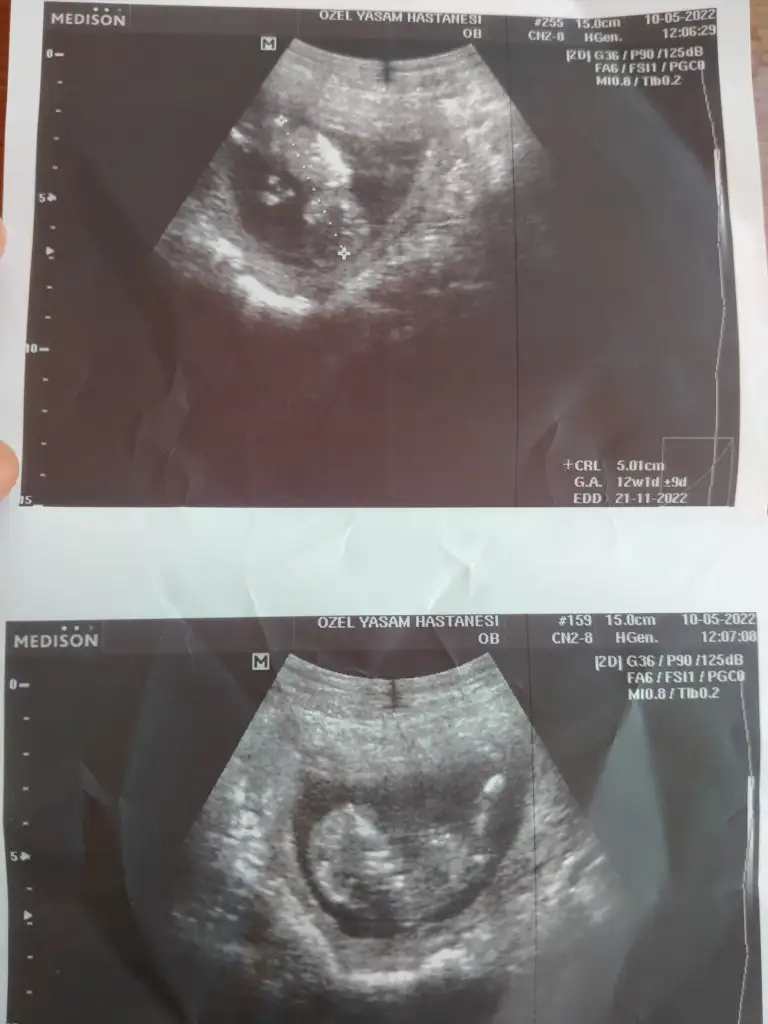

Merhabalar, daha önce bana yorum yapmıştınız ama iki doktor da farklı bişey söyledi o yüzden tekrar sormak istedim. Hatta bakalım hangimiz haklı çıkıcaz falan dediler 😁 12+3 karından bakıldı.

• 69F07FB8-3472-459A-A84D-06053AE5F39A.webp

69F07FB8-3472-459A-A84D-06053AE5F39A.webp

42,8 KB · Görüntüleme: 60

• 35F4B265-9D3D-49ED-8989-D15C2485F6E4.webp

35F4B265-9D3D-49ED-8989-D15C2485F6E4.webp

31,5 KB · Görüntüleme: 65

canım sana ne demiştim bilmiyorum. ama bu görüntüler sanki erkek diyor